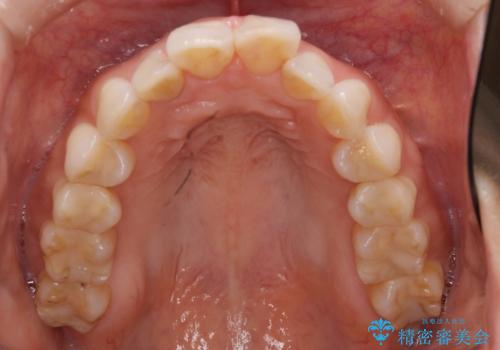

ワイヤーによる抜歯矯正でガタガタと深いかみ合わせの改善

上下の前歯の叢生とかみ合わせが深い過蓋咬合という状態でした。

かみ合わせの深さを改善するのに時間がかかり、予定よりも治療期間が長期化しましたが、整った歯並びへ改善することができました。